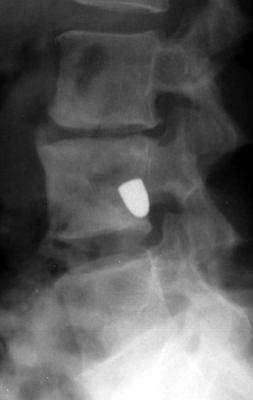

Two sets of frontal and lateral radiographs, separated only by time, which reveal the "tumbling bullet sign"--which is simply a bullet which changes its location and orientation within a solitary bone cyst. This sign serves two purposes. It is documentation of the evolution of a solitary bone cyst as a corollary of trauma, and reveals the free movement of the foreign body within the confines of the lesion establishing its cystic rather than solid nature. It is similar to the fallen fragment sign.

- Click on the image for a larger versionA - Click on the image for a larger versionB - Click on the image for a larger versionC - Click on the image for a larger versionD